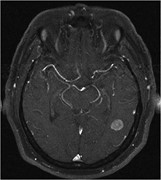

Cerebral metastases from Merkel cell carcinoma: long-term survival

S. Honeybul

Journal of Surgical Case Reports, Volume 2016, Issue 10, October 2016, rjw165, https://doi.org/10.1093/jscr/rjw165